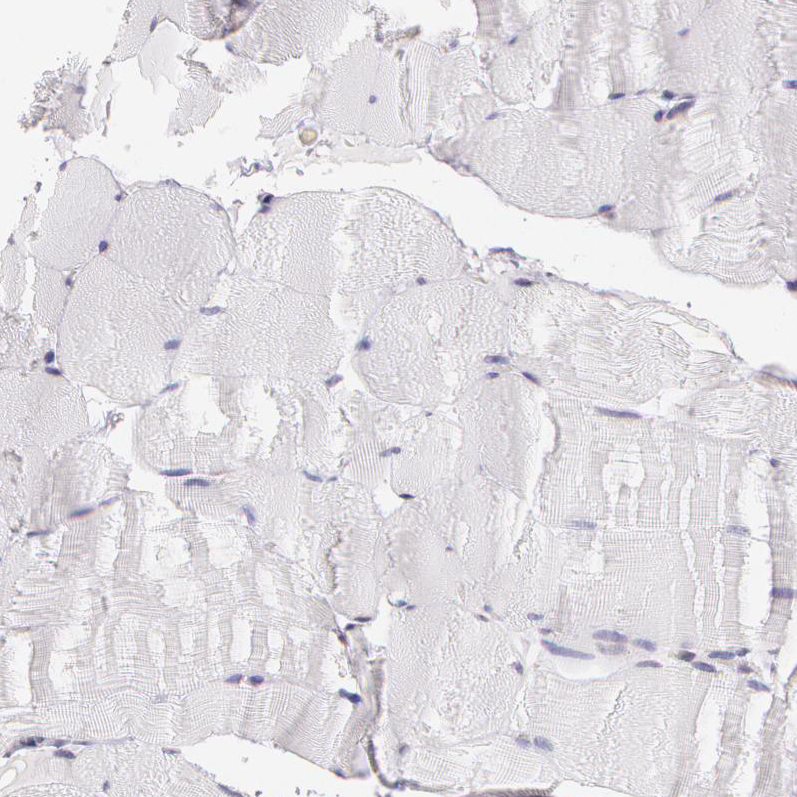

Immunohistochemistry analysis in human cerebral cortex and skeletal muscle tissues using HPA001462 antibody. Corresponding APP RNA-seq data are presented for the same tissues.